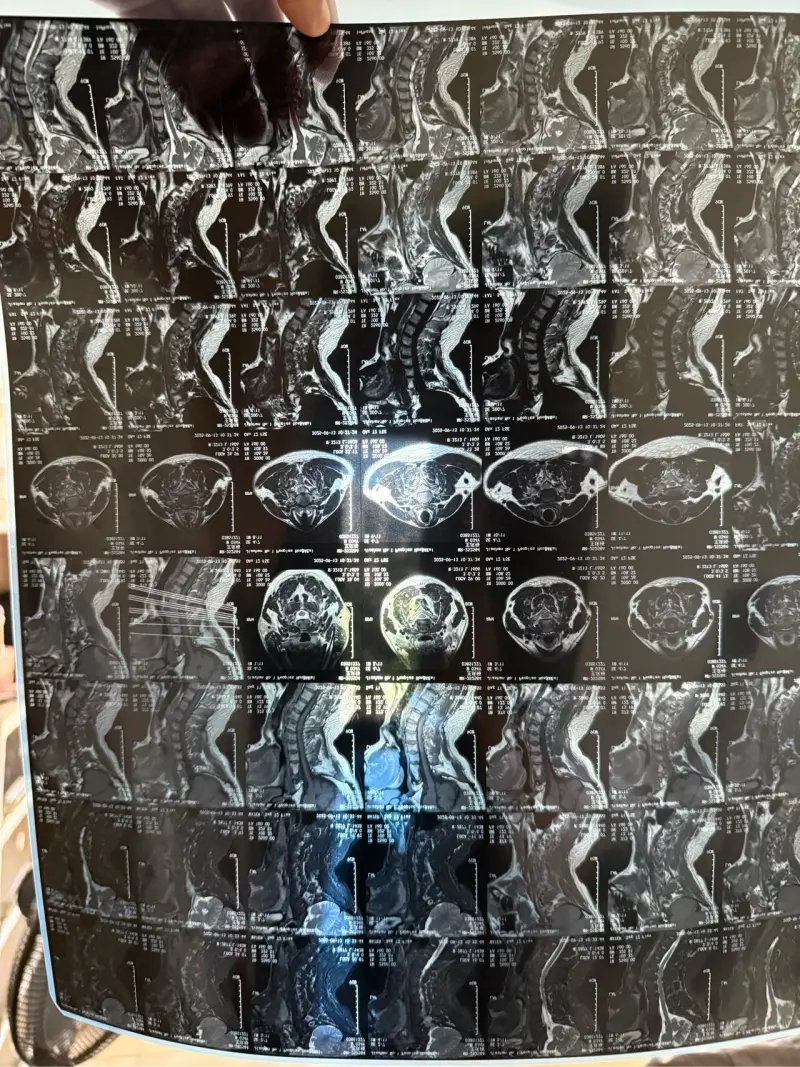

关于颈椎这个话题,我可能是最有资格说话的,我做了三次颈椎手术,脖子前面一次,脖子后面两次,我的颈椎上打着4个钢板,12根钢钉,一个金属网兜,我要把我的片子拿出来让你们看,能把大多数人吓得翻个跟头,很多人第一反应这他妈是机器人的颈椎吧?全是铁

不是突出,是非常非常严重的突出,再拖几年就要坐轮椅了,主治大夫说这是他近几年以来做的最复杂的一个手术,他们流水线手术一般三个小时左右就做好了,我花了6个多小时,把大夫累屁了,我都不好意思跟他说,我10年前上一次在你们这做颈椎手术花了七八个小时,把医生都快整脱水了,麻药都续了两次

确实,刚开始的大夫也说,从医以来我的病例是最复杂的之一,郝院长为我这个手术思索了一天方案,然后决定自己来。